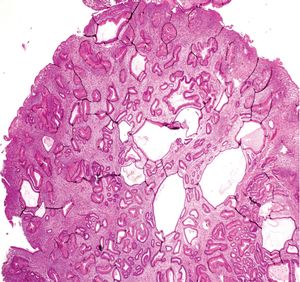

| 유년성 용종 | 상부 위장관 및 결장 | 확장된 고유층을 가진 낭성 확장된 샘 | 본질적으로는 아니지만, 이형성이 발생할 수 있음 | ![]() | 유년성 용종증 증후군, Cronkhite–Canada 증후군에서 동일한 용종 |

| 유년성 용종 | 상부 위장관 및 결장 | 확장된 고유층을 가진 낭성 확장된 샘 | 본질적으로는 아니지만, 이형성이 발생할 수 있음 | 유년성 용종증 증후군, Cronkhite–Canada 증후군에서 동일한 용종 | |